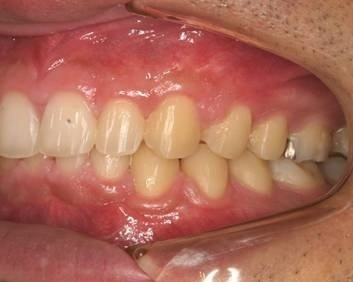

Case 2

主訴: 出っ歯が気になる

診断: アングルⅡ級Ⅰ類 上顎前突

治療方針  :

患者さんは18歳の女性あった。U-1 to FHは1S.D.を超えて大きく、下顎歯列に軽度の叢生を認めた。上顎左右側第一小臼歯および下顎左右側第二小臼歯の抜歯を行い、マルチブラケット装置により上顎前歯部の審美的改善とⅠ級関係の咬合様式を獲得することとした。

治療期間 : 2年1カ月

費用:

診断費30000円、装置費用600000円、保定装置費用50000円、月1回の調整費4000円  (全て税別)

【 治療前 】

【 治療後 】